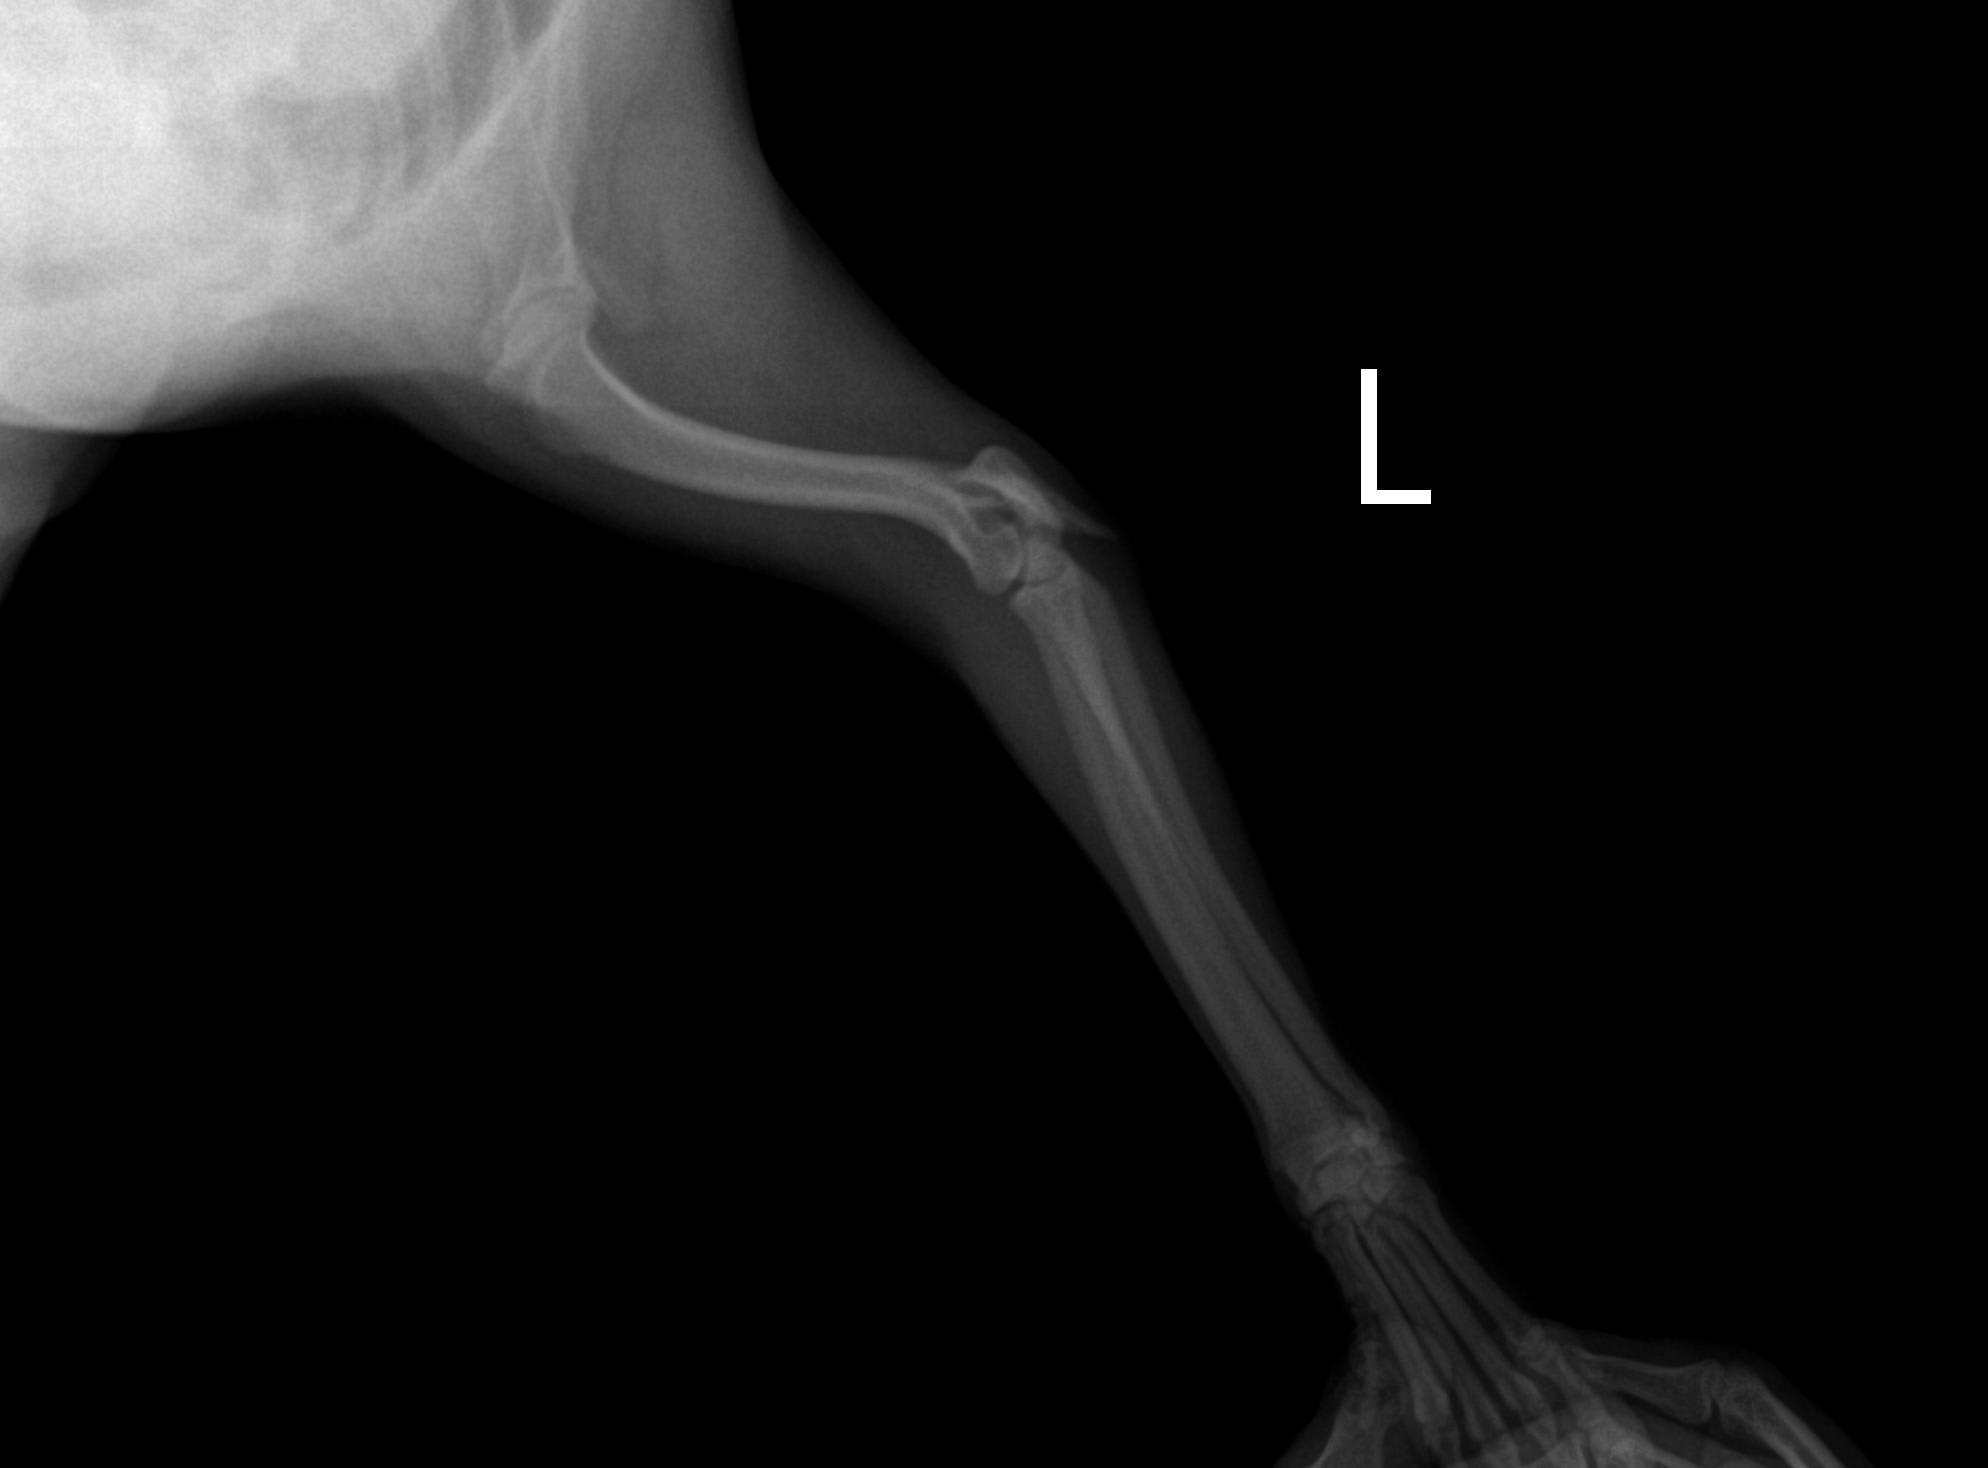

Pet's info: Dog | Pomeranian | Male | unneutered | 1 year and 3 months old | 11 lbs

My dog is pomeranian. Hisleft elbow fractured 3weeks ago Without surgery will it be healed??

Hi, thanks for using Petco Pet Education Center, formerly Petcoach! Sadly that type of fracture should be treated surgically. There is are tendons that attach there and a tension band wire is needed for an avulsion fracture of the olecranon. I would suspect it will not heal. If it has been 3 weeks you should have another X-ray taken to see how it is doing. I wish you the best!